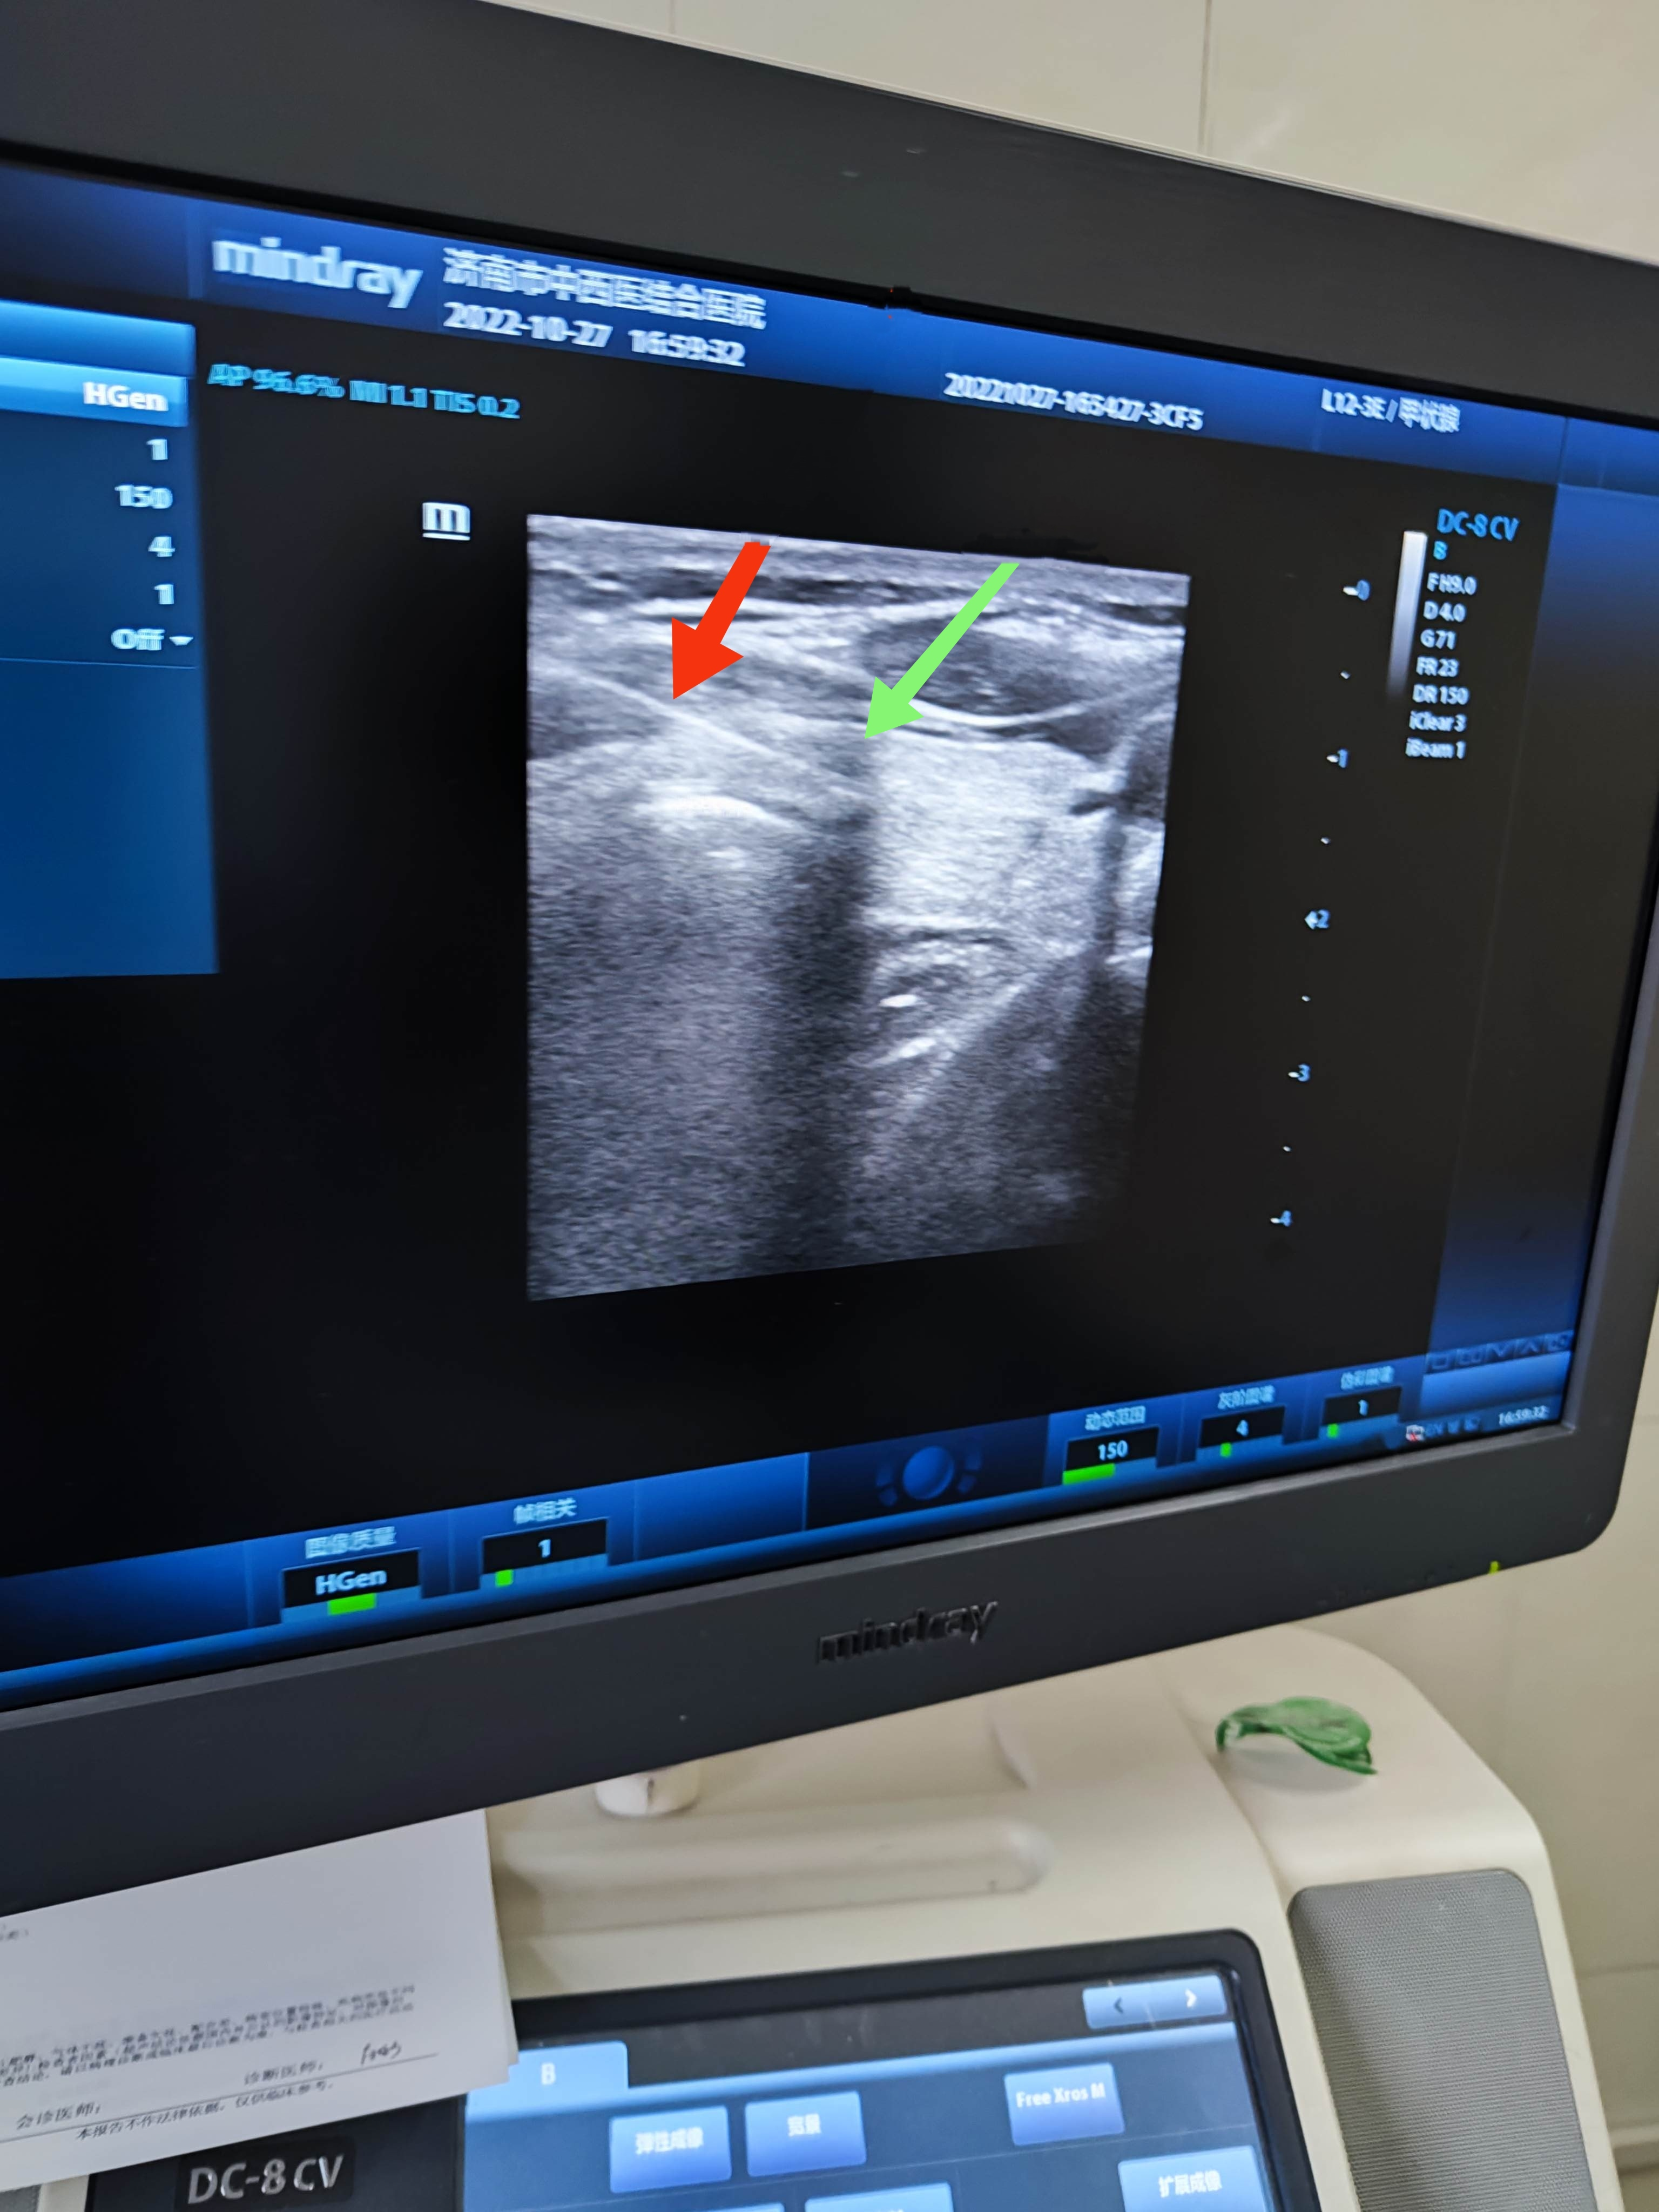

穿刺圖像

放(fàng)大圖像